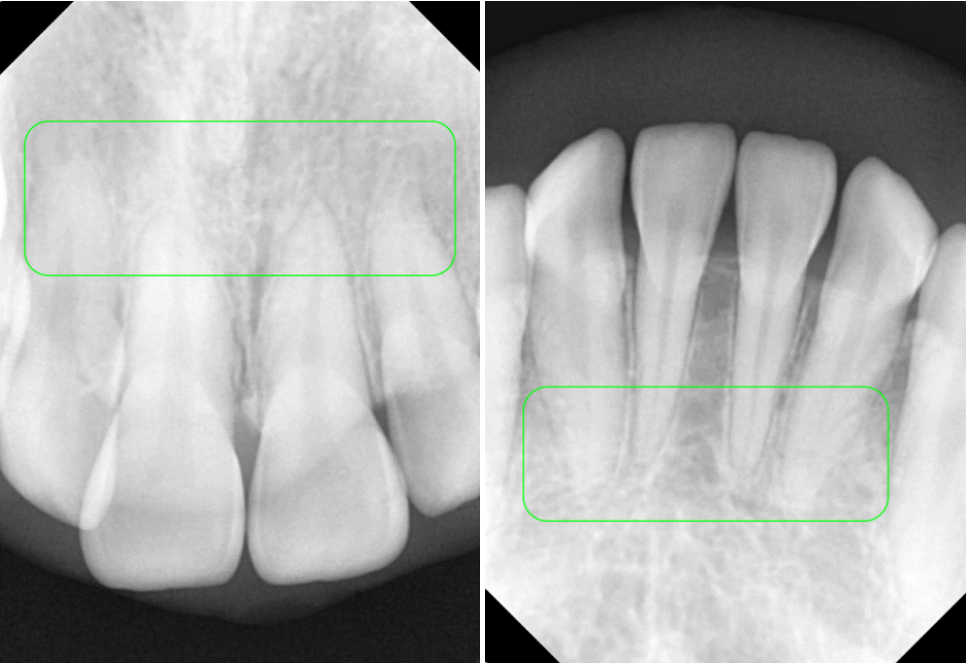

파노라마에서 오른 쪽 위를

자세히보면 유치가 남아있고,

제 2소구치(작은 어금니)가

올라오지 못하는 모습을 볼 수 있습니다.

치아 뿌리는 ‘치근’이라고 하며,

어떠한 이유로 짧아지는 현상을 ‘치근 흡수’라 부릅니다.

이 ‘치근 흡수’는 치아교정에서 나타날 수 있는

대표적인 부작용으로, 과학적으로 입증된 사실인데요.

치근 길이가 선천적으로 짧거나 형태가 비정상적인

흡수가 과도하게 일어나는 경우도 있기 때문에,

이동 과정에서도 조금 더 신경을 써야됩니다.

따라서 위와 같은 정밀검사를 통해 유심히 살펴보고

분석해야되는 부분 중 하나입니다.